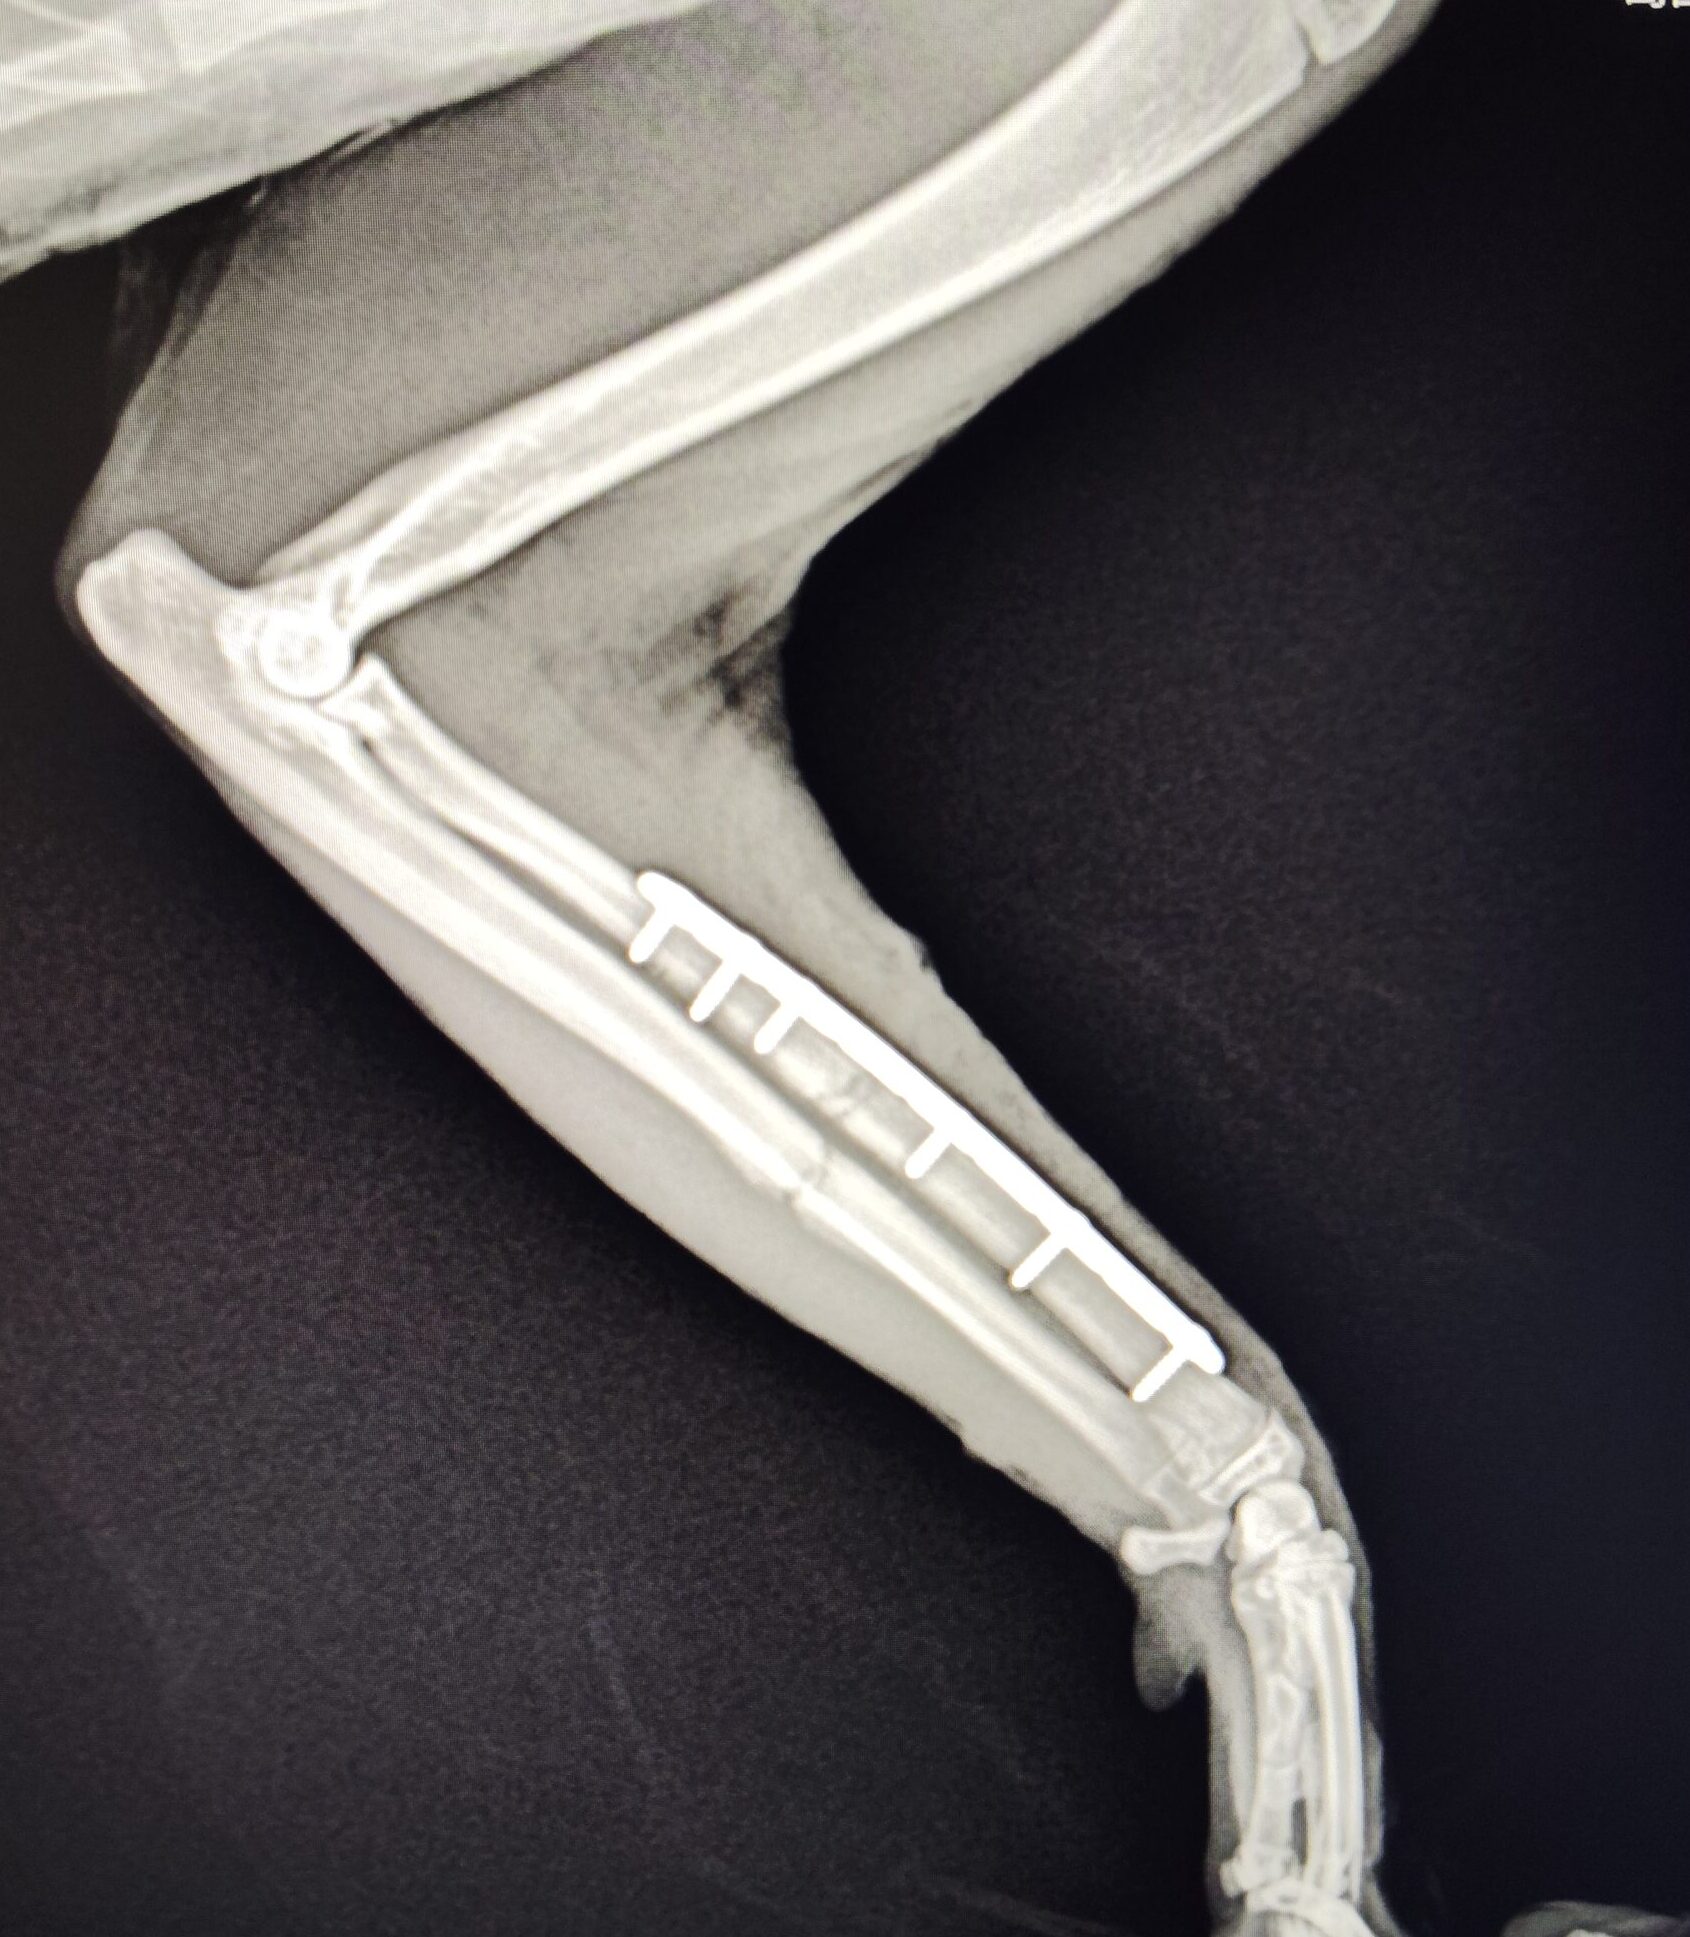

- レントゲン検査にて結腸拡張(便塊の貯留)を確認